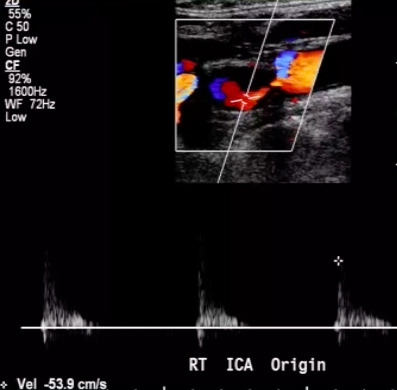

Patient has Lt ICA 100% occlusion. Rt carotid system shown below. PSV = 208 cm/s in proximal Rt ICA.

Most likely diagnosis?

mild Rt ICA stenosis (<50%)

since Lt ICA is 100% occluded, there should be elevated Rt CCA velocities (CCFA*)

plaque in proximal Rt ICA is <<50% ⇒ elevated velocities across Rt ICA are likely due to CCFA

*CCFA = compensatory carotid flow augmentation